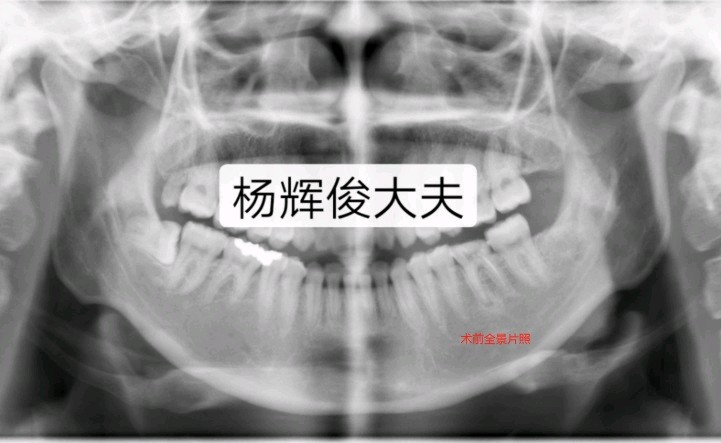

一、颏成形术

口内进路的水平截骨颏成形术是矫正各种颏部畸形的基本术式,无论是作为正颌外科的辅助手术,还是作为独立的面部整形美容手术,其应用越来越普遍。也是目前矫治各种颏部形态异常的最佳手术。

适应症:颏后缩畸形、颏前突畸形、颏过长畸形、颏过短畸形、颏部不对称畸形;